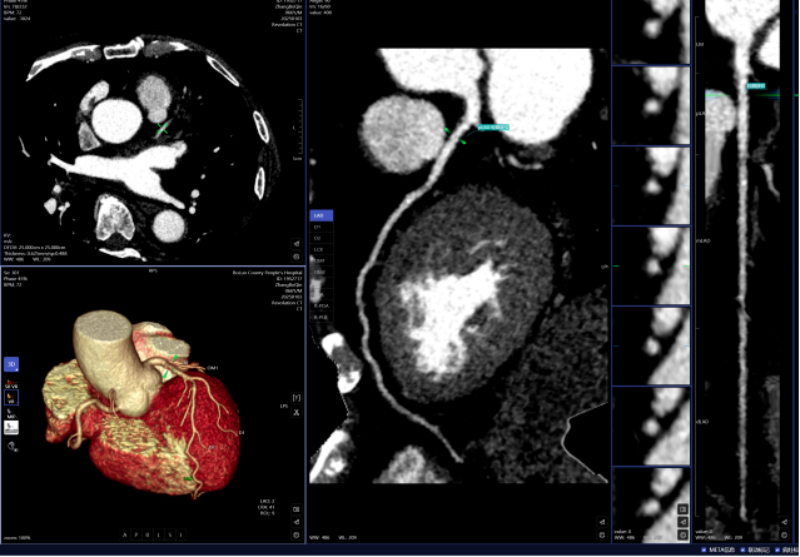

血管诊断、脑血管灌注成像

头颈部CTA、冠状动脉CTA、肺动脉CTA及肢体CTA是一种无创、低风险、快速的检查方法,能够清晰识别血管狭窄、畸形或斑块,明确病灶与周围正常组织的位置关系,为治疗方案的制定提供有力依据,能提高患者生存率,缩短高危患者急救救治时间。

以往,放射科医生进行头颈部CTA和冠状动脉CTA重建后处理,需要医生应用工作站手动处理,耗时约20-30分钟。而AI人工智能辅助诊断系统通过计算机视觉和深度学习技术,仅需5-10分钟即可完成影像重建的后处理计算,一键生成精准的三维重建图;系统还能自动标记血管名称、快速判断斑块性质,并根据最新指南对狭窄程度进行分级诊断等,帮助医生快速定位病变节段,准确分析斑块类型及狭窄程度;对脑血管灌注成像进行快速重建和诊断,大幅缩短患者等候检查和获取诊断报告的时间。